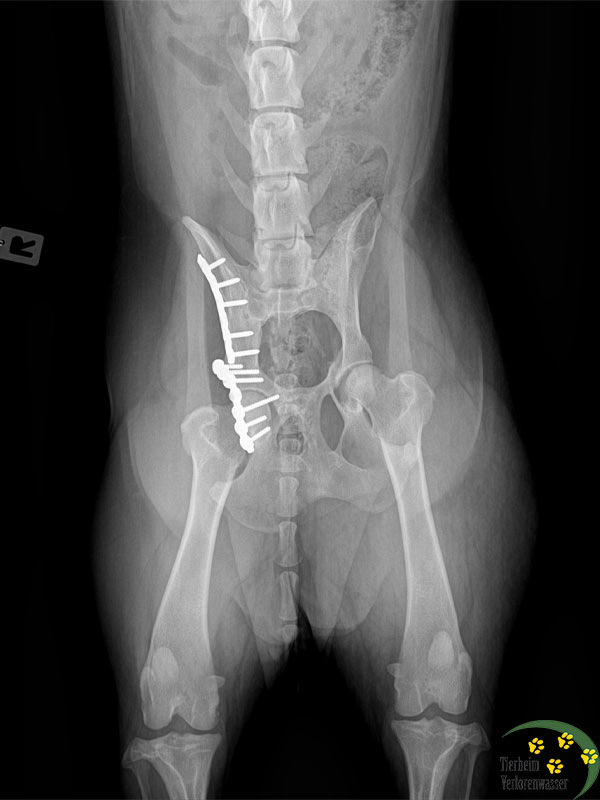

komplizierte operatationen hund tierschutz 1Unsere Sorgenkinder Nela (Foto im Aufwachraum nach der OP) und Frieda (Foto beim Spaziergang vor der OP) haben es gut überstanden.

Beide hatten arge Gelenkprobleme. Deshalb fuhren wir zu einem spezialisierten Chirurgen nach Berlin. Bei Frieda musste der Tierarzt in einer komplizierten Operation die Platten entfernen, die früher einmal bei ihr eingesetzt worden waren. Es hatten sich Schrauben gelockert. Frieda konnte nicht mehr richtig laufen und litt große Schmerzen.